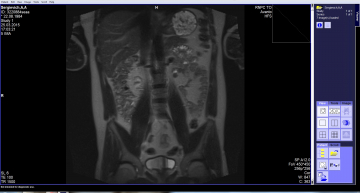

Здравствуйте, меня зовут Наталья, мне 35 лет. С 20 лет у меня болела спина, а 2 года назад боли почти прекратились, но стали млеть руки и ноги.    После обращения к невропатологу предварительный диагноз врач поставил демиелинизирующее заболевание ЦНС. Было сделано МРТ головы и шеи. Демиелинизирующее заболевание ЦНС не подтвердилось, а обнаружилось: Межпозвонковый остеохондроз шейного отдела позвоночника, осложненный медианной протрузией диска С6-С7.    Пройдено лечение лекарствами. Состояние ухудшилось: мление рук и ног уменьшилось, а головокружение и боли в голове, а так же в спине увеличились. Резко стало бросать то в жар, то в холод, при условии, что признаков ОРЗ нет.   При повторном обследовании МРТ шейного, грудного и пояснично-крестцового отдела позвоночника мне выдали протокол исследования. Печатаю дословно....   При исследовании шейного, грудного и поясничного отдела позвоночника костно-деструктивных изменений не обнаружено. Отмечается снижение сигнала и высота м/п дисков, сглаженность шейного и поясничного лордоза, субхондральный склероз замыкательных пластин, признаки начальных артрозных разрастаний в м/п суставах, грыжи Шморля Т7-12. Отмечаются:   - протрузии дисков С4-5, С5-6, С6-7 до 2,5 мм с сужением СМК до 11 мм, нерезкой компрессией переднего арахноидального пространства, нерезким сужением м/п отверстий   - медианная грыжа диска Т6-7 до 3 мм сужением СМК до 14,5 мм, компрессией переднего арахноидального пространства   - протрузии дисков Т7-8, Т8-9 до 1,5 мм с нерезкой компрессией переднего СА пространства   - протрузии дисков L4-5   L5-S1 до 2,7 мм с сужением СМК до 16 мм, дурального мешка до 11 мм с нерезкой его компрессией, нерезким сужением входа в м/п отверстия   В теле Т6 определяется гиперинтенсивный в обоих режимах очаг размерами 8*9 мм, аналогичный очаг определяется в теле L3 размерами 5*6 мм   Сагиттальный ПК на уровне тел позвонков С4-5 до 13,5 мм (сужен), Т5-6 до 15 мм,  L4-5 до 15,5 мм   Релаксационные характеристики и конфигурация спинного мозга не изменены.   Пре и паравертебральные ткани не изменены.   Сигнальные характеристики крестца, копчика и подвздошно-крестцовых сочленений не изменены.   ЗАКЛЮЧЕНИЕ: МРТ признаки дегенеративно-дистрофических изменений позвоночника ( остеохондроз, спондилоартроз, грыжи Шморля), протрузии выше указанных м/п дисков, грыжа диска Т6-7, Гемангиомы Т6, L3.   Подскажите пожалуйста, как быть и что делать????  Заранее спасибо.

Добрый день! Гемангиомы позвонков - это доброкачественные образования, которые встречаются у 5-10% здоровых людей. Делать с ними ничего не нужно, только наблюдать в динамике. Дегенеративно-дистрофические заболевания позвоночника лечатся у невролога, симптоматика у них самая разнообразная (это и головокружение и головные боли и прочее). Нередко в таких ситуациях дополнительно назначают УЗИ сосудов шеи, выполняют МР-ангиографию шеи. Можно выполнить КТ-исследование шеи с болюсным усилением для исключения аномалий и патологии вертебробазилярной области. Судя по данному заключению МРТ, ничего страшного в позвоночнике не обнаружено. Грыжа межпозвонкового диска иногда требует нейрохирургического вмешательства.